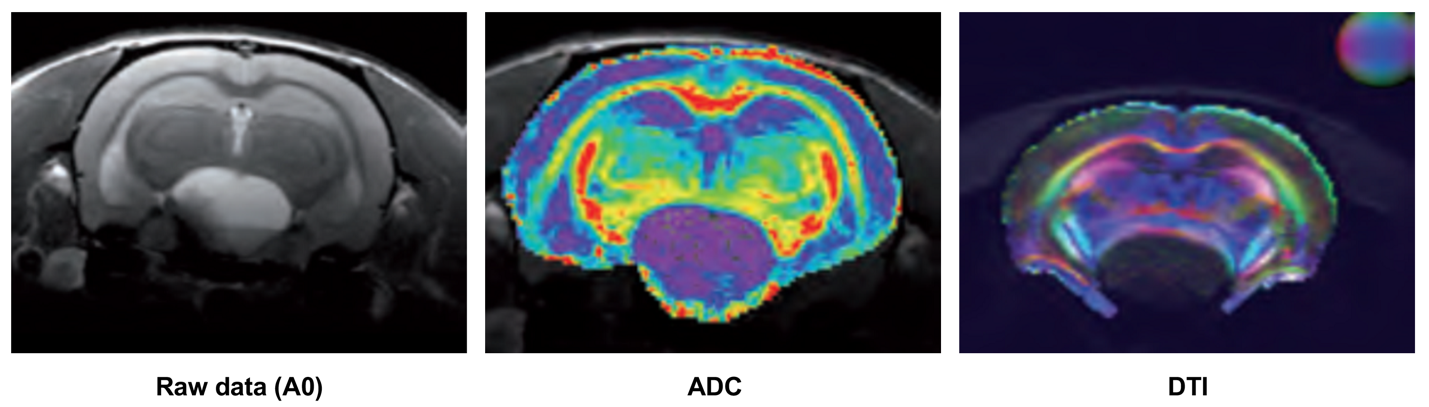

Animal: Rat

Sequence: DTI with TE/TR = 25/1500 ms, Voxel Size = 200µm × 200µm × 1mm